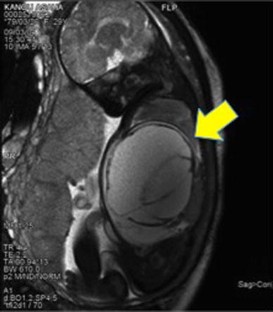

Case 1 was an 11-year-old boy diagnosed with rupture of the esophageal varices and hypersplenism due to congenital extrahepatic portal hypertension. Because of persistent hypersplenism and thrombocytopenia, he underwent meso-Rex bypassing with a left iliac vein graft interposed between the umbilical vein and the superior mesenteric vein. Case 2 was a neonate with a large hepatic tumor (mesenchymal hamartoma) that developed abdominal compartment syndrome at birth. The tumor was removed by right hepatectomy with excision of the portal vein bifurcation at 3 days of age. Porto-Rex bypassing was accomplished by end-to-end anastomosis between the portal vein trunk and the umbilical vein.

Sufficient hepatopetal portal flow through the umbilical vein was achieved in both patients and maintained for over 16 and 13 months, respectively. Although hypersplenism remained in Case 1, intrahepatic portal vein branches gradually widened and the cavernoma in the hepatic hilum disappeared within 2 months. Neither patient had symptoms or signs of portal hypertension at the most recent follow-up.